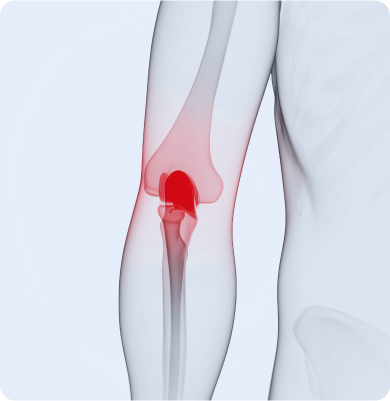

관절을 보호하는 연골이 노화, 반복된 사용 등으로 닳아 없어지며 통증과 염증을 유발하는 질환

노화로 인한 연골의 퇴행성 변화가 원인이며 비만, 반복적인 관절 사용, 외상, 유전적 요인 등도 발생에 영향을 줍니다.

무릎관절의 슬개골 아래 연골이 연해지고 손상되는 질환

슬개골에 반복적인 압력이 가해지거나 외상, 잘못된 자세, 근력 불균형 등으로 인해 연골에 손상이 생기며 발생합니다.

무릎 앞쪽에 있는 슬개골(무릎뼈) 아래 연골이 부드러워지고 손상되는 질환

반복적인 무릎 사용, 과도한 운동, 무릎의 잘못된 정렬, 외상 등이 원인이 될 수 있습니다. 특히 달리기나 계단 오르내리기 등 무릎을 자주 쓰는 활동에서 자주 발생합니다.

관절 주변의 윤활 역할을 하는 주머니인 점액낭에 염증이 생긴 질환

반복적인 마찰이나 압박, 과사용, 외상, 감염 등이 주요 원인입니다. 무릎, 어깨, 팔꿈치, 엉덩이 등 자주 움직이거나 압력이 가해지는 부위에서 자주 발생합니다.